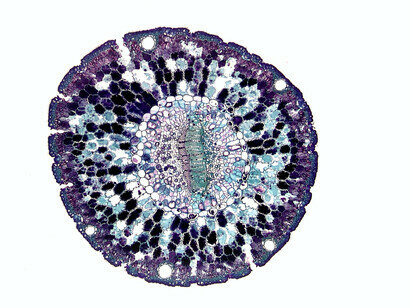

A importância das células-tronco na medicina moderna foi descrita recentemente nesta revista9. As células-tronco reabastecem as células mortas. As células-tronco reparam e mantêm músculos, ossos e nosso sistema imunológico neuroendócrino. Mitocôndrias, ribossomos e outras organelas saudáveis são muito importantes para regular as funções vitais de todas as células. As principais proteínas devem ser quebradas e refeitas quando necessário. Assim como o corpo inteiro precisa manter a homeostase geral, as células dentro dele precisam manter uma rede equilibrada de homeostase proteica (proteostase)10. As proteínas são produzidas em uma organela chamada o ribossomo. As proteínas devem se dobrar em suas estruturas tridimensionais adequadas para manter a saúde. As proteínas mal dobradas podem formar placas que levam a danos oxidativos e doenças como o mal de Alzheimer. As proteínas adequadamente dobradas que controlam o metabolismo celular devem ser degradadas quando não são necessárias. Tanto as proteínas mal dobradas quanto as normais podem ser degradadas por uma organela chamada a proteassoma. A energia necessária para esses e outros processos celulares essenciais é fornecida pelas mitocôndrias. Juntas, elas mantêm uma proteostase saudável. A perda da proteostase e a exaustão das células-tronco são duas das marcas registradas do envelhecimento10. A homeostase das células-tronco é mantida pelo controle da tradução do ARN em proteínas nos ribossomos e pela quebra das proteínas nos proteossomos quando necessário. Há também uma camada de controle acima do ADN (genoma), chamada epigenoma. Ela pode ativar ou desativar a transcrição do ADN em ANR ao anexar ou remover marcadores, como grupos metil. Há também um epitranscriptoma que modifica as proteínas que foram transcritas. Por exemplo, a ligação e a remoção de grupos fosfato nas proteínas podem ativá-las ou inativá-las. O epitranscriptoma, o controle translacional e a degradação de proteínas trabalham juntos para regular os proteomas, que ajudam a controlar a identidade e a função das células-tronco11. O envelhecimento está associado a uma diminuição da capacidade de regeneração dos tecidos e a um aumento da incidência de doenças degenerativas12. Como resultado, a função das células-tronco diminui em muitos tecidos durante o envelhecimento. Isso é especialmente verdadeiro no sangue e no sistema imunológico neuroendócrino.

Ao mesmo tempo, a terapia com células-tronco tem grande potencial na medicina regenerativa13-14. As células-tronco podem ser totipotentes, pluripotentes, multipotentes ou unipotentes. As células totipotentes em um zigoto podem se diferenciar em todos os tipos de células. As células-tronco pluripotentes (CTPs) podem se diferenciar em praticamente qualquer tipo de célula. Elas podem ser células-tronco embrionárias (CTEs) ou células das camadas germinativas (mesoderma, ectoderma e endoderma). As células-tronco multipotentes só podem se diferenciar em células intimamente relacionadas. Por exemplo, as células-tronco hematopoiéticas podem se transformar em glóbulos vermelhos, glóbulos brancos e plaquetas. As células-tronco musculares unipotentes só podem se diferenciar em células musculares. As células-tronco mesenquimais (CTMs) são células-tronco específicas de tecidos que são usadas para reparar tecidos danificados e são úteis na medicina regenerativa. As CTMs podem gerar ossos, cartilagens e outros tipos de tecido. O uso de CTMs não causa problemas éticos em comparação com as CTEs e são menos tumorigênicas do que as CTPs. As vesículas extracelulares das células-tronco também podem ser úteis na medicina regenerativa14-15.